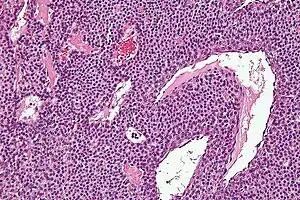

Micrograph of a glomus tumor. H&E stain.

Histologically, glomus tumors are made up of an afferent arteriole, anastomotic vessel, and collecting venule. Glomus tumors are modified smooth muscle cells that control the thermoregulatory function of dermal glomus bodies. As stated above, these lesions should not be confused with paragangliomas, which were formerly also called glomus tumors in now-antiquated clinical usage. Glomus tumors do not arise from glomus cells, but paragangliomas do.

By histopathology, glomus tumors can be termed as follows:[7]

• Solid glomus tumor (75% of cases): Consisting predominantly of glomus cells, with poor vasculature and rare smooth muscle cells.

• Glomangioma (20% of cases): Tumors with a prominent vascular component.

• Glomangiomyoma (5% of cases): Tumors with prominent vascular and smooth muscle components.